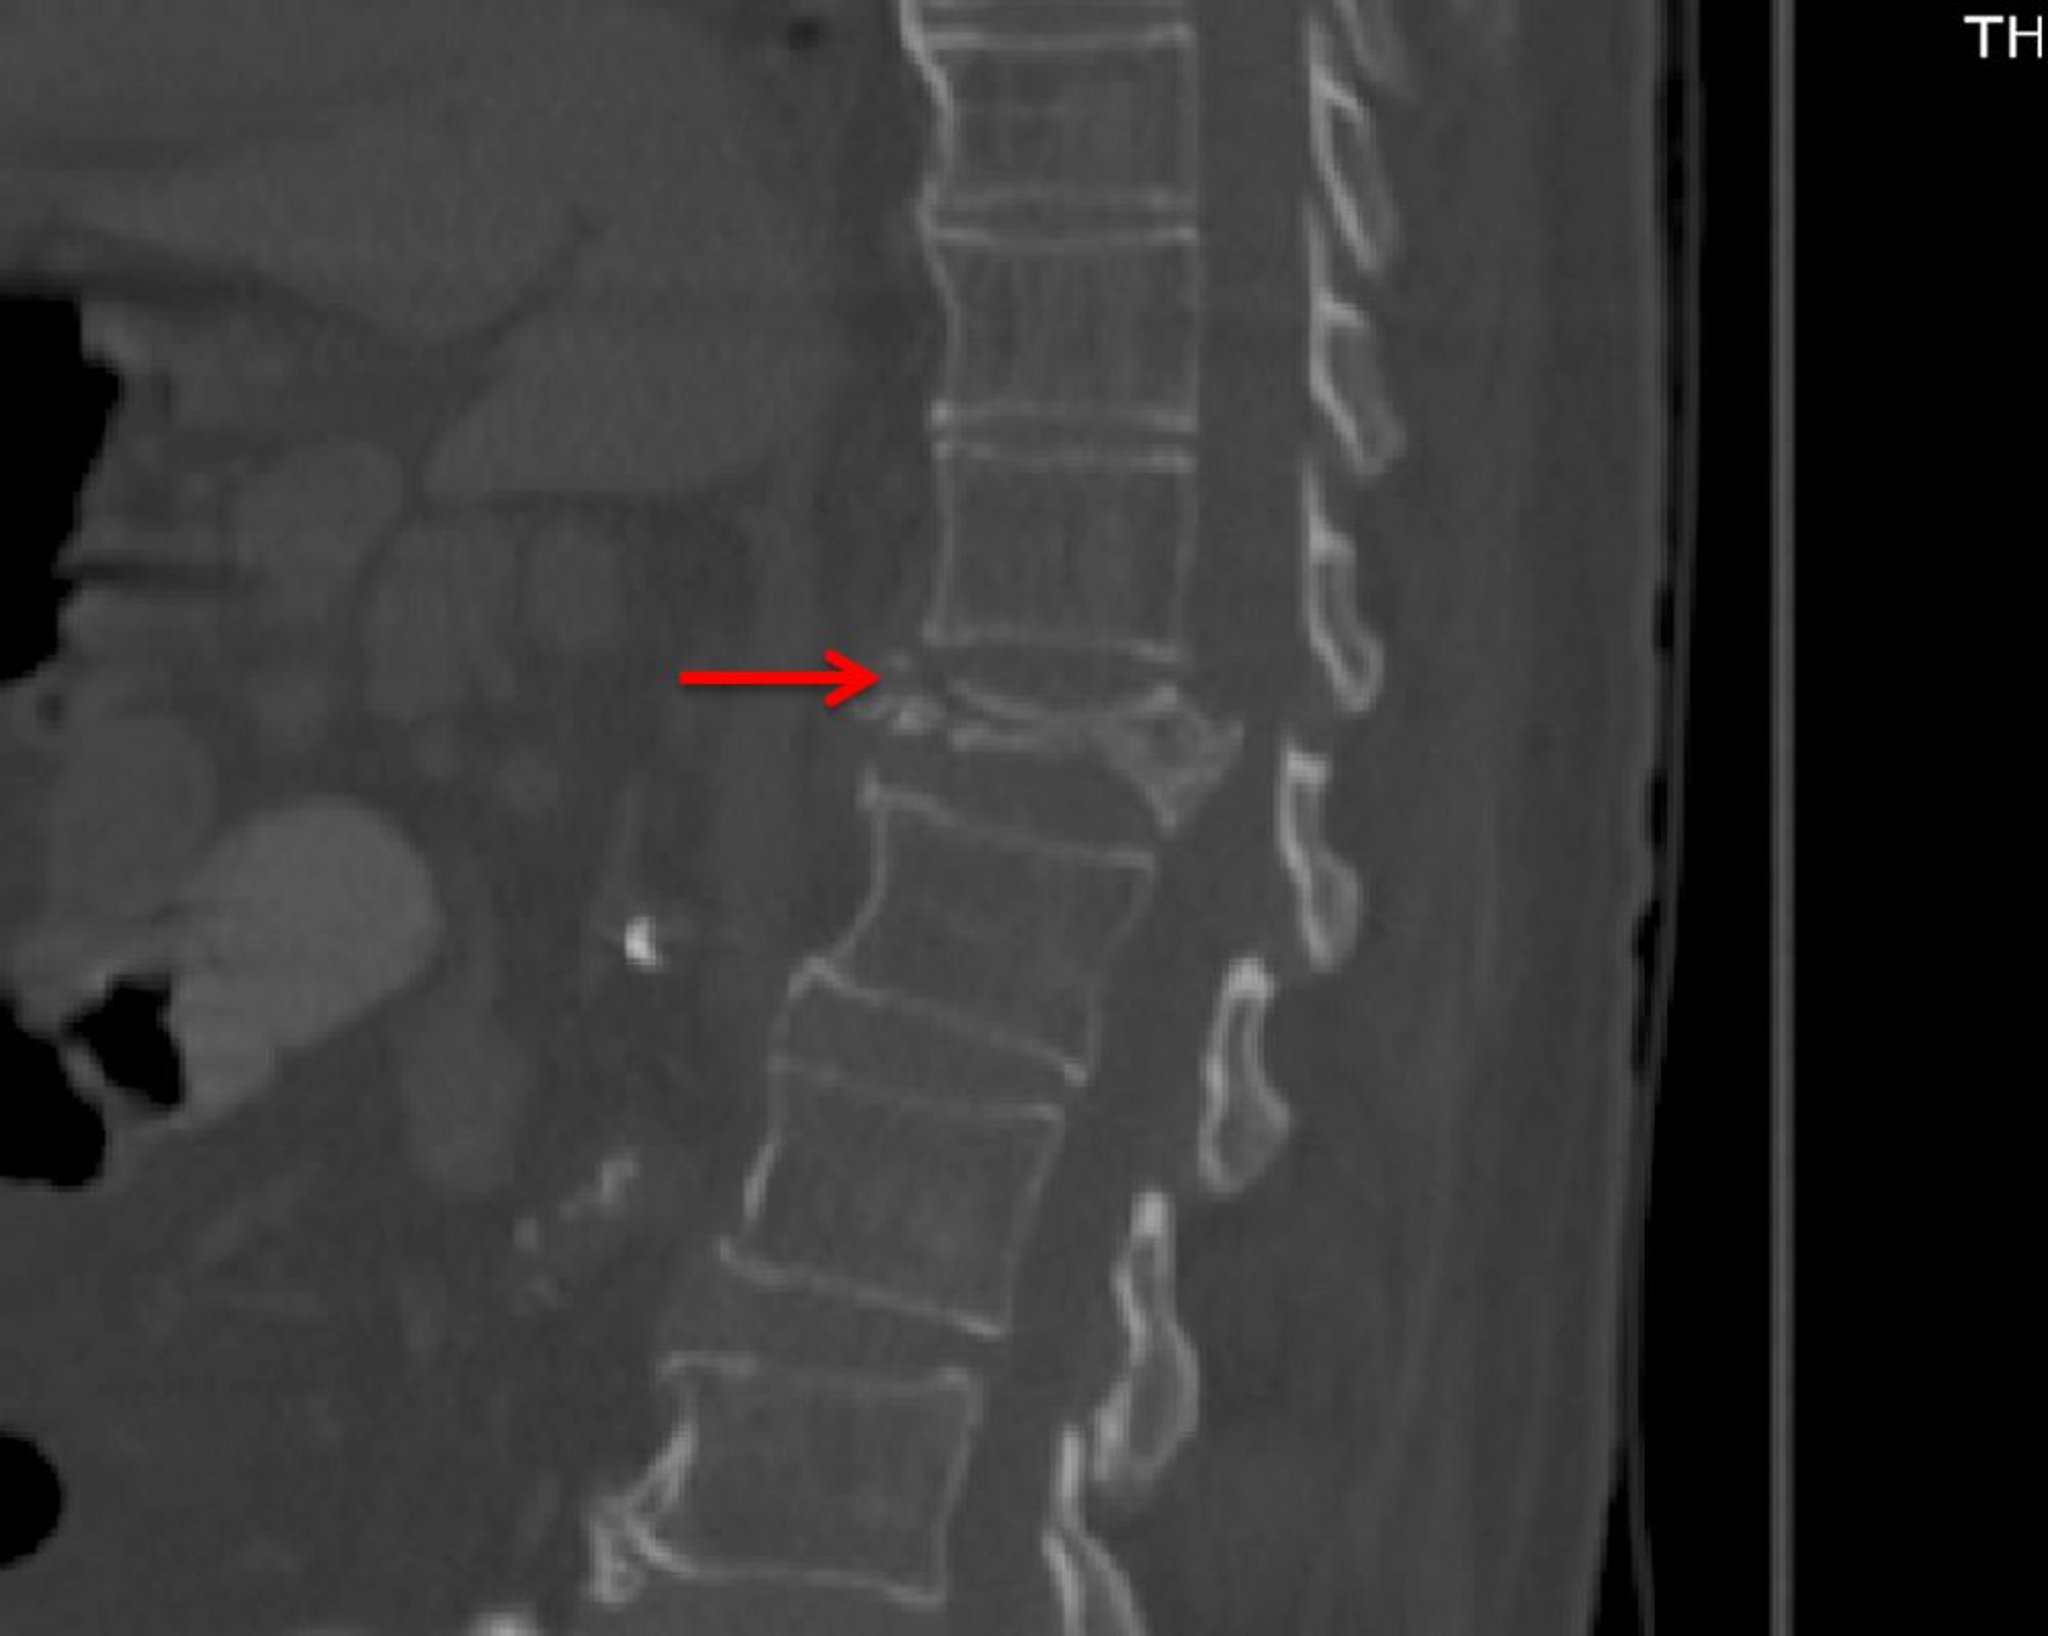

Schwere Wirbelkörperkompressionsfraktur (CT)

Diese CT-Aufnahme (sagittale Ansicht) zeigt eine ausgeprägte Kompressionsfraktur von T12 mit einer leichten degenerativen Erkrankung (z. B. Osteophyten im vorderen Wirbelkörper) an anderer Stelle.